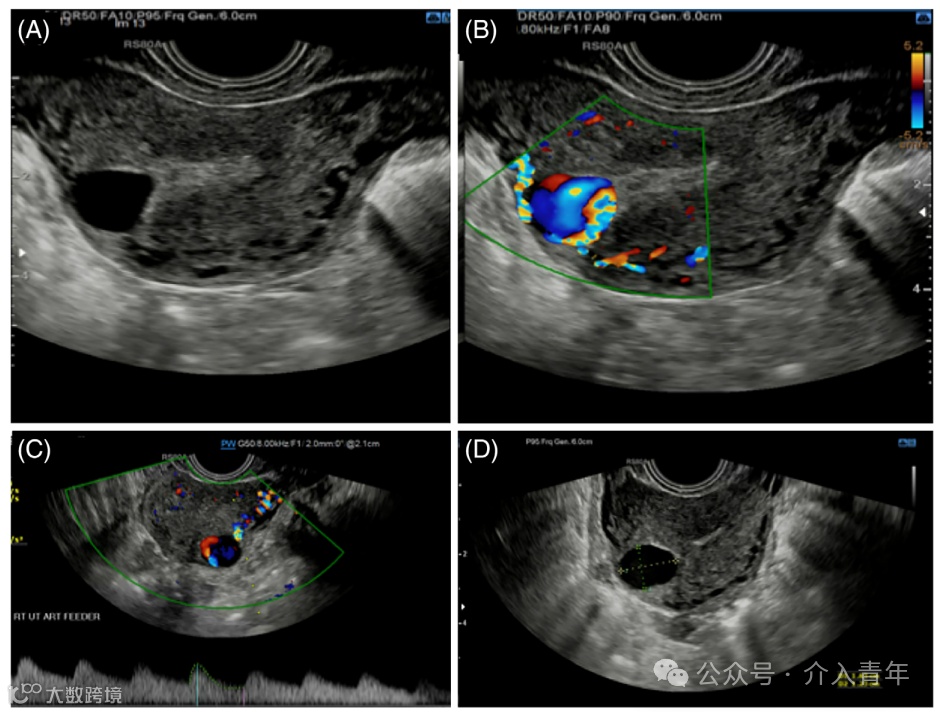

图3:图2患者行经阴道超声(TVUS)引导下凝血酶注射。

(A)经阴道横断面彩色多普勒超声图像显示,阔韧带处卵巢动脉分支供血的假性动脉瘤。

(B)TVUS引导下凝血酶注射。黑色线代表Chiba针的穿刺路径,其针尖(箭头)位于假性动脉瘤内(星号)。

(C)经阴道横断面超声图像显示假性动脉瘤内有高回声凝血块(星号)。

(D)经阴道横断面彩色多普勒超声图像证实假性动脉瘤内无血流。